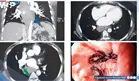

Pancreatitis necrosante como complicación pos-COVID-19 en hombre con shock e insuficiencia multiorgánica